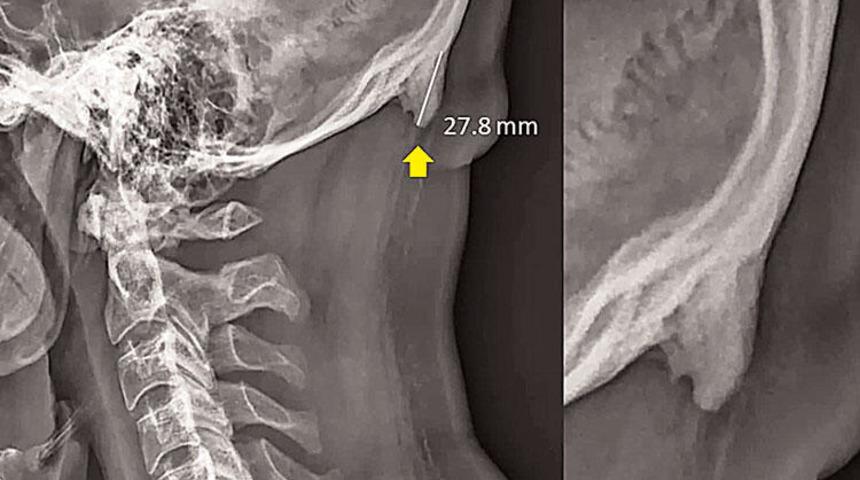

Avustralya’daki Sunshine Coast Üniversitesi’den Dr. David Shahar ve Prof. Mark Sayers isimli iki bilim insanının, 18-30 yaş arasındaki 218 kişinin röntgen çekimlerini inceleyerek yürüttüğü araştırmada, bu kişilerin neredeyse yarısının kafatası şeklinin yoğun cep telefonu ve tablet kullanımına bağlı olarak ‘değiştiği’, boynuzumsu bir çıkıntıya benzediği belirtildi. Araştırmaya göre, gününün büyük kısmında teknolojik aletlere kafasını eğerek bakan gençlerin, kafatasındaki oksipital kemik denen bölge, görünür şekilde belirginleşmeye başlıyor. Her 4 gençten birinde görülen bu durum, dijital ekranlar karşısında geçirilen süreyle ilgili endişelere bir yenisini daha ekliyor.

Bilim insanı Shahar, 20 yıldır klinik tedavi uzmanı olduğunu belirterek “Ancak sadece son 10 yıldır hastalarımın kafatasındaki büyümeyi gözlemliyorum” dedi. Ensenin üstünde sivrilen 10-30 milimetre arasında değişen çıkıntıya, ‘dış oksipital kabartı’ deniyor. Dış oksipital kabartıya, taşınabilir dijital cihazlar yaygınlaşmaya başlamadan önce daha çok yaşlı insanlarda rastlandığı, gençlerde ise oldukça nadiren rastlandığı belirtiliyor. Kafatasındaki çıkıntının, iskelet yapısında uzun süre baskıya maruz kalmış kişilerde rastlanması hesaba katıldığında, uzun süre cep telefonu ekranına bakmanın da benzer etkiyi yarattığı söylenebilir.